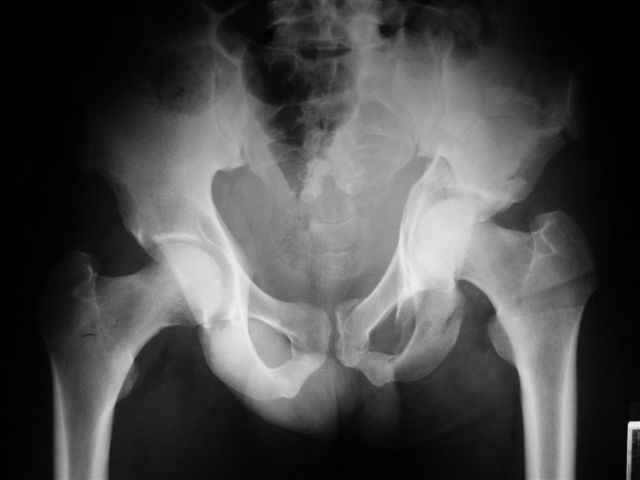

Уважаемые коллеги,43 летний мужчина, попав в автоаварию 13.10.2004, получил оскольчатый перелом обеих колонн левой вертлужной впадины.

На рентгенограммах - высокий двухколонный перелом вертлужной впадины с нарушением конгруэнтности, имеется обратная клиновидность суставной щели.